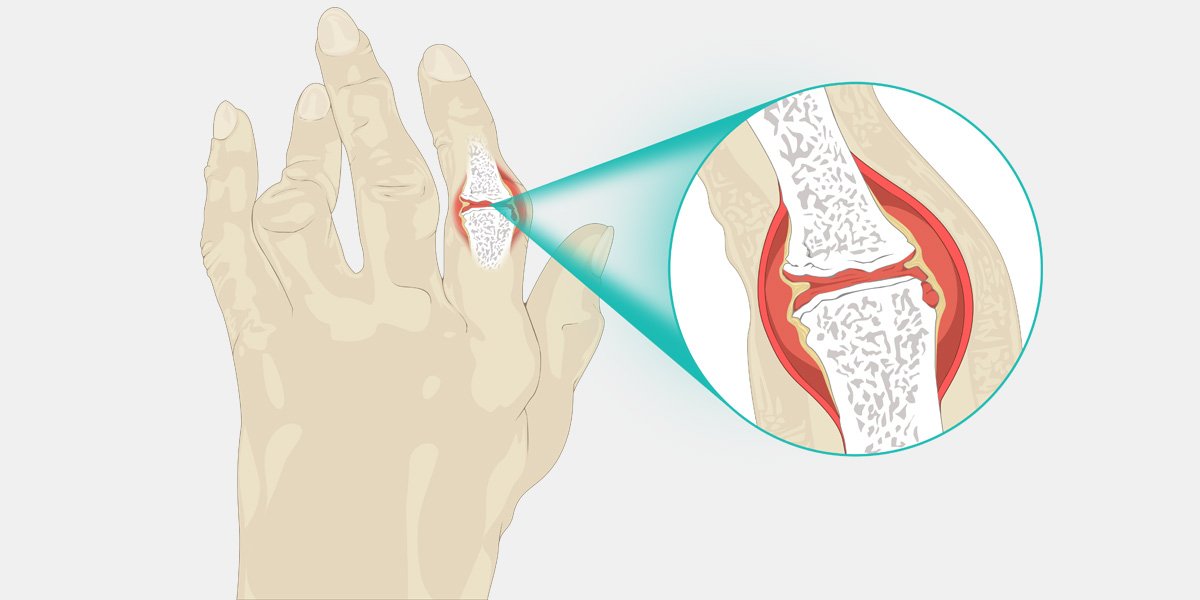

و بالتالي يزيد من سمكه ، فينتج عنه في النهاية تدمير للغضاريف والعظام. كما تضعف الأربطة والأوتار التي تربط أجزاء المفصل معاً فينتهي الامر بفقدان المفصل شكله الطبيعي.